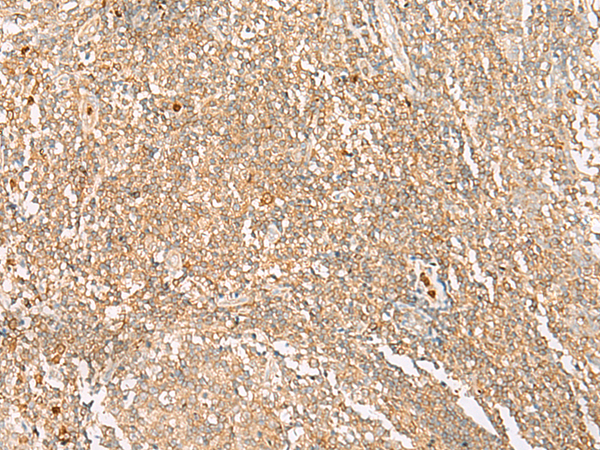

分类: 科研抗体货号: P04090别名: CT1.6; MAGE6; MAGE3B; MAGE-3b应用: IHC反应种属: Human